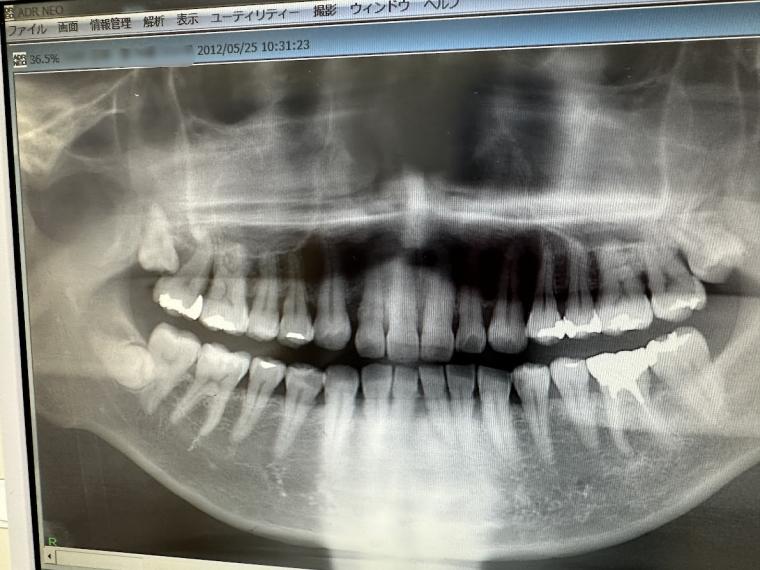

たとえば今回の例では、

十数年前に一度ご来院いただいていたものの、

治療をしっかり進めていくタイミングで

通院が途切れがちになり、

その後は間が空いてしまいました。

(2012年)